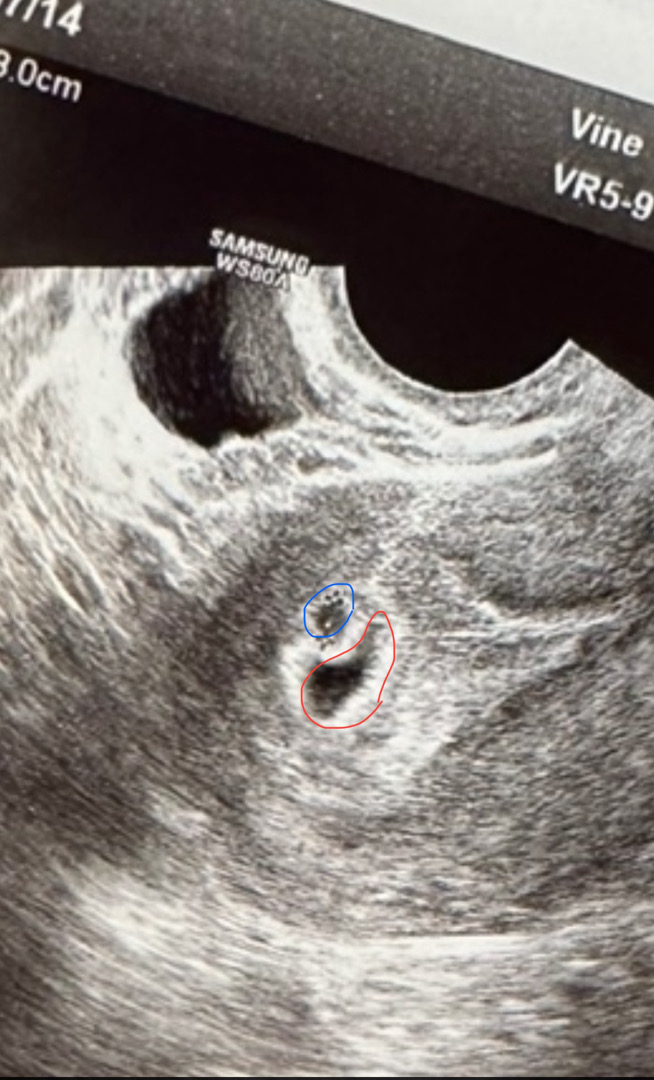

파란 동그라미가 애기집이고 빨간부분이 피고임이에요.. 병원에서는 착상은 잘 됐으나 옆에 피고임이있다고 하시더라구요 너무 걱정됩니다ㅜㅜ 5주 2일차 정도 되는데 원래 이때 애기집이 저렇게 작을까요ㅜㅜ? 저처럼 초기에 피고임 현상 겪어보신 산모님들 이야기 듣고싶어요 무서워요ㅠ